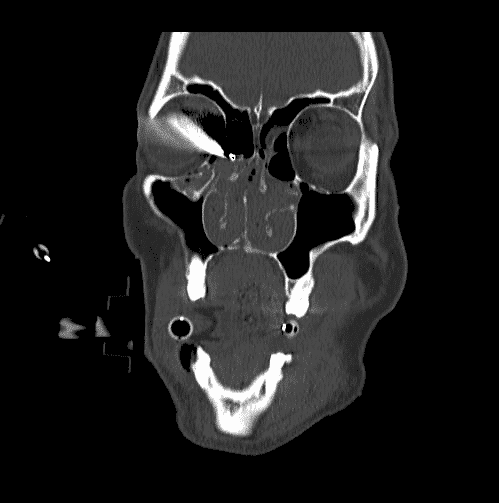

Зображення: орбітальний перелом

Зобр. 15. Комп’ютерна томограма, що демонструє переломи дна та медіальної стінки лівої орбіти.

Автор фотографії: Maj Brett Davies.